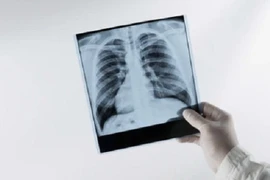

Phổi tắc nghẽn mãn tính là căn bệnh nguy hiểm đứng thứ 4 trong số các nguyên nhân gây tử vong cao nhất tại Việt Nam. Chẩn đoán sớm và can thiệp kịp thời sẽ giúp ích cho việc điều trị bệnh.

Bệnh phổi tắc nghẽn mạn tính (COPD) phổ biến, có hơn 380 triệu người mắc trên toàn thế giới. Đối với những người mắc COPD, việc thay đổi lối sống, áp dụng các biện pháp chăm sóc sức khỏe phù hợp là vô cùng quan trọng.

Theo Tổ chức Y tế thế giới, bệnh phổi tắc nghẽn mạn tính (COPD) là nguyên nhân gây tử vong đứng thứ 3 trong các nguyên nhân gây tử vong và đứng thứ 5 về gánh nặng bệnh tật toàn cầu.